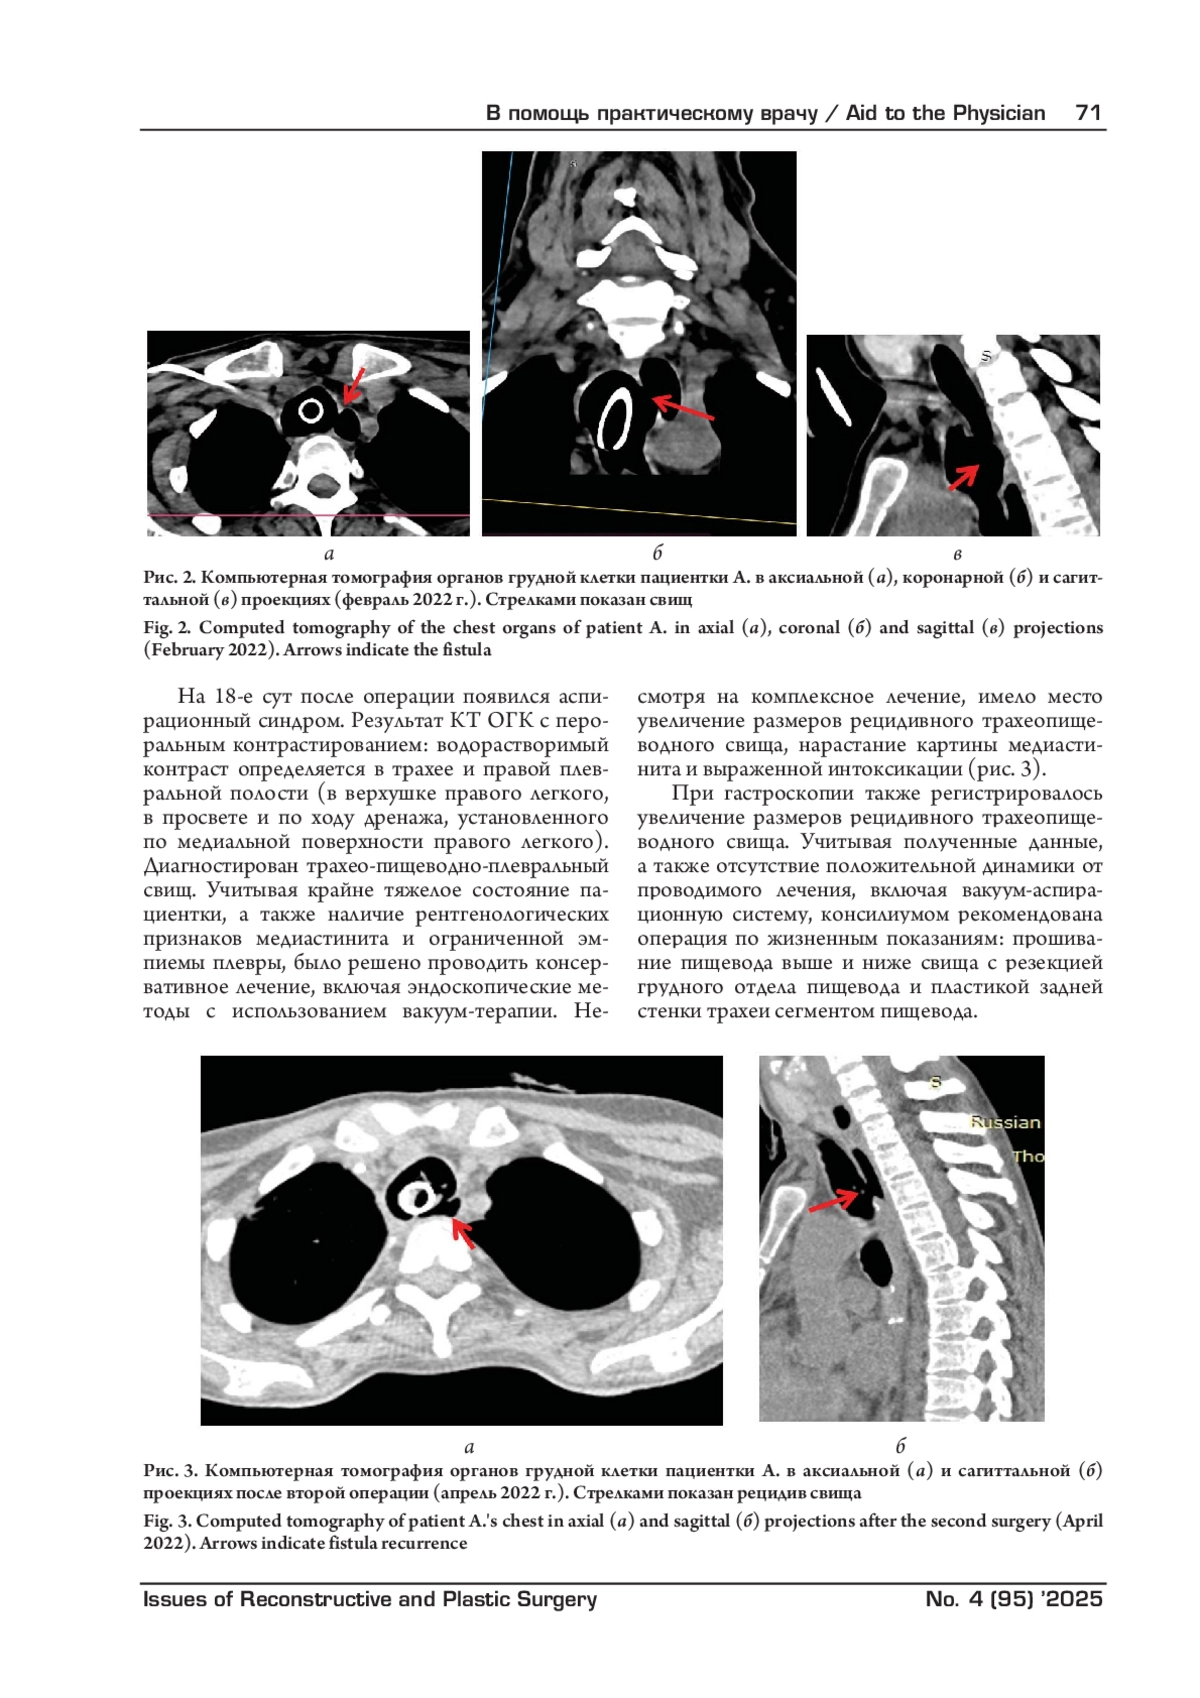

В статье описан нестандартный хирургический подход к лечению пациентки с рецидивирующим трахеопищеводным свищом. Применен метод пластики задней стенки трахеи заплатой из пищевода. Такой подход в условиях дефицита тканей и длительно существующей инфекции позволил изолировать пораженный участок задней стенки трахеи и создать дополнительную защиту механического шва. Выбранный подход привел к полному излечению и улучшению качества жизни пациентки.